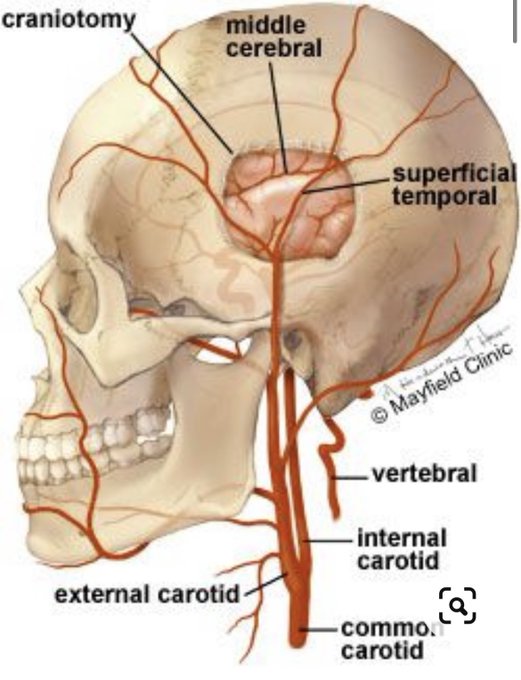

It worries me that a person with a scalp vessel supplying their brain (STA-MCA Bypass or EDAS) will unintentionally wear too tight sunglasses/ reading glasses and cause ischemia.